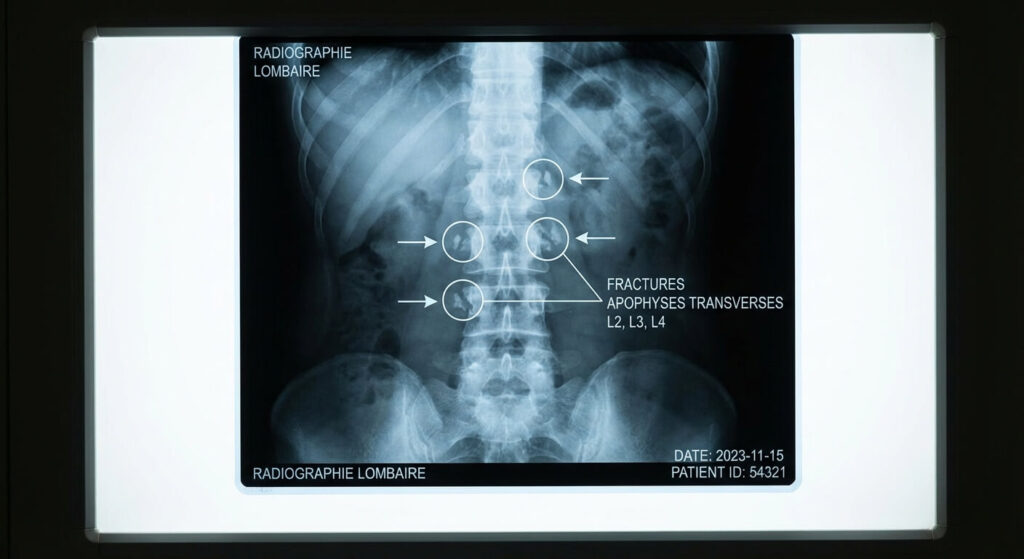

Mécanisme de la blessure et diagnostic radiologique

Une fracture affectant plusieurs apophyses transverses du côté droit ou gauche de la région lombaire n’est jamais anodine quant à la force de l’impact subi. Anatomiquement, ces petites protubérances osseuses sont profondément enfouies sous une épaisse masse musculaire. Pour les briser, il faut qu’un choc direct majeur vienne écraser la zone (choc latéral lors d’un accident de la route, impact lors d’un sport de contact comme le rugby), ou qu’une flexion latérale brutale provoque une contraction si féroce du muscle que celui-ci arrache littéralement le fragment d’os auquel il est attaché (on parle alors de fracture par avulsion).

Le tableau clinique initial est spectaculaire. Le patient ressent une douleur fulgurante en bas du dos, souvent latéralisée, qui s’accentue dramatiquement à la moindre tentative de flexion, de torsion du buste ou même lors d’une simple toux. Les muscles adjacents se contractent violemment (spasme de défense), rendant la marche très difficile. Le diagnostic de certitude est posé par l’imagerie médicale. Si la radiographie standard peut suffire à repérer les fractures sur L2, L3 et L4, le scanner (tomodensitométrie) reste l’examen de référence. Il permet d’écarter toute lésion associée sur le corps vertébral ou sur les organes internes voisins (comme les reins, très proches de l’apophyse L2 et L3).